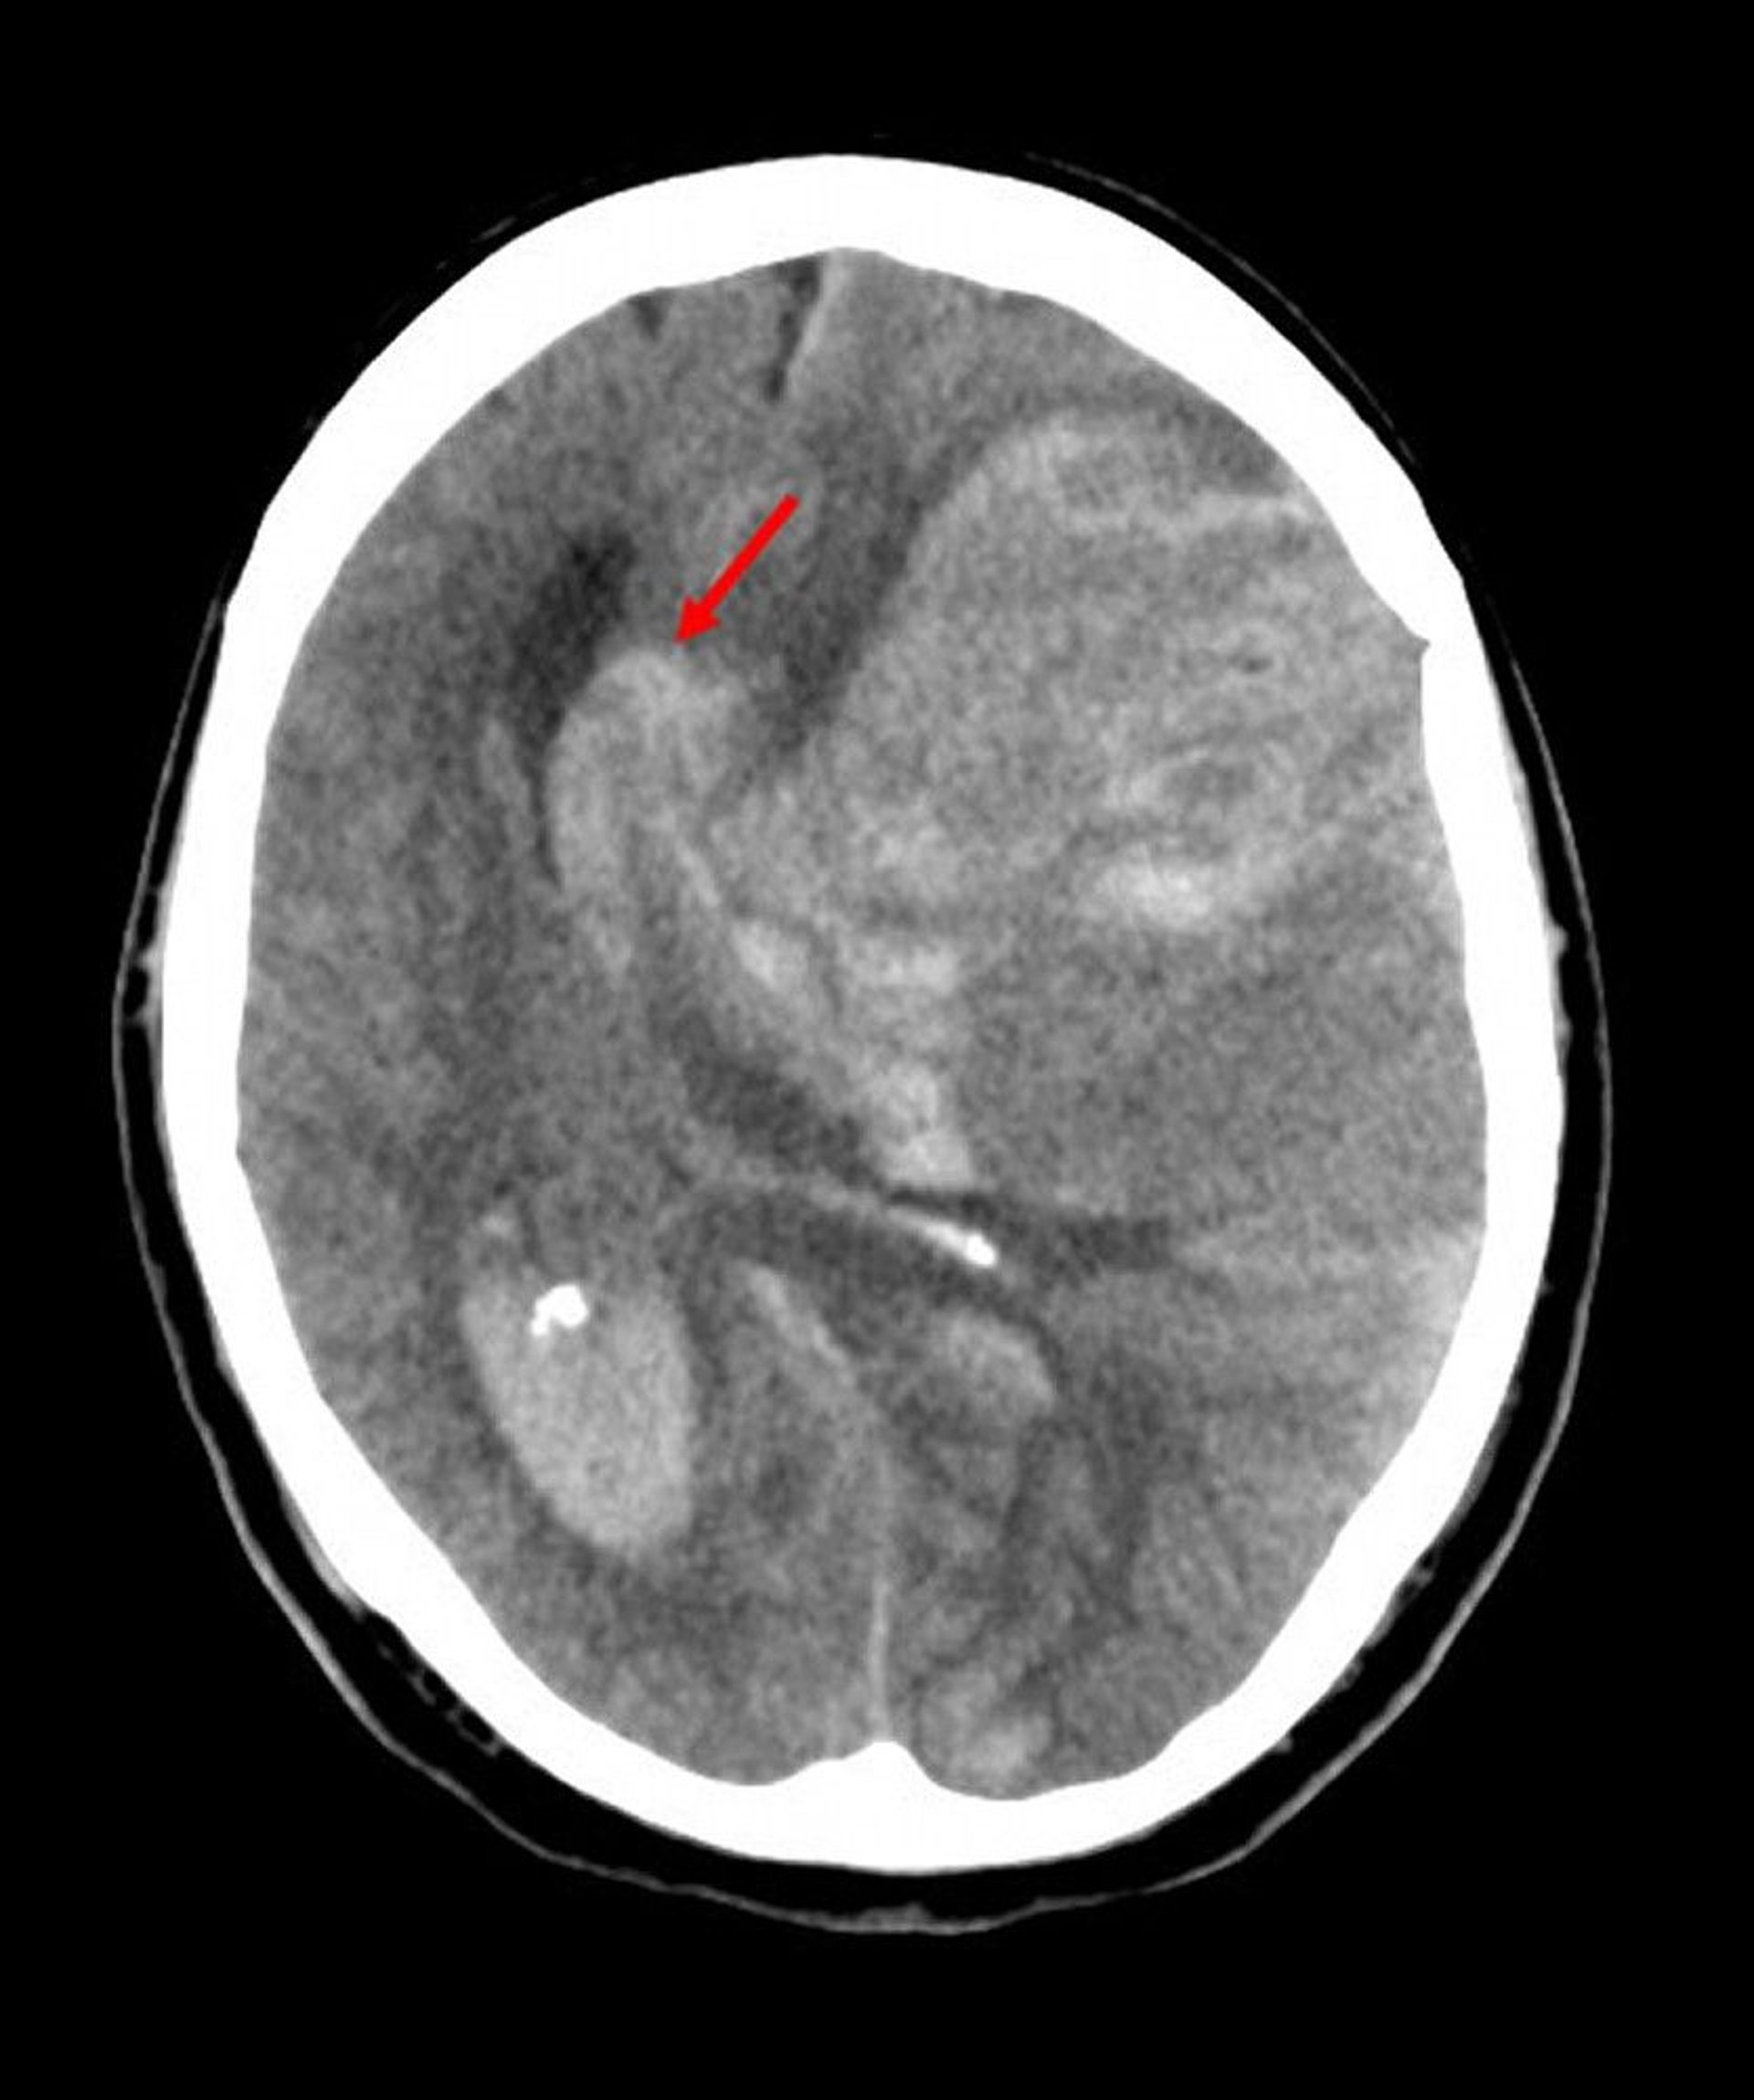

Subfalcine Herniation

Subfalcine herniation is the most common type of cerebral herniation. In this image, the left brain has herniated under the free edge of the falx cerebri (arrow) because hemorrhage from an infarct in the middle cerebral artery has increased intracerebral pressure.